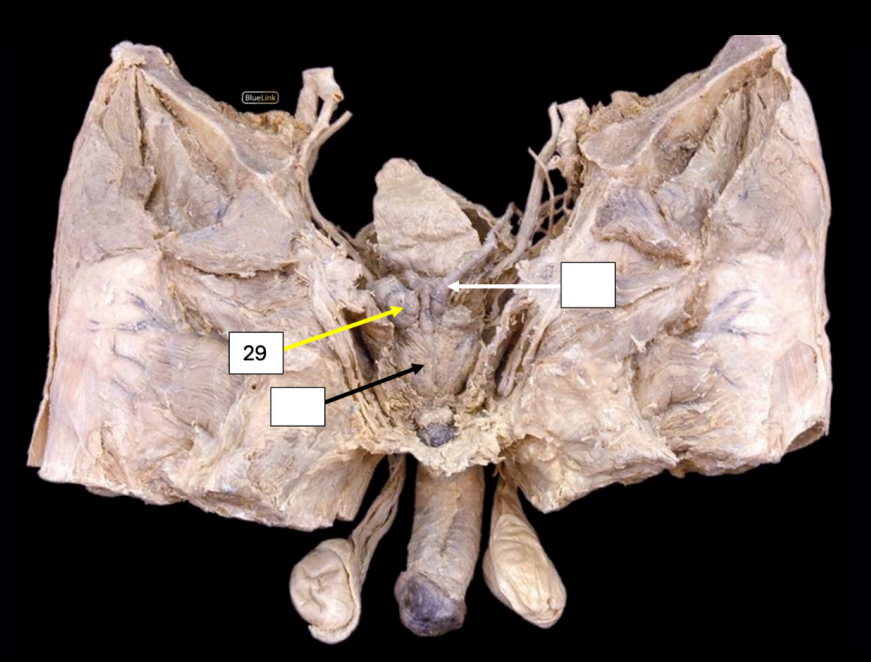

Body of the Uterus

Side Question:

What are the four primary supports of this structure?

Pelvic Diaphragm (Levator ani) - Main Support

*Cardinal Ligament (at the sides)

*Pubocervical Ligament (Anterior)

*Uterosacral Ligament (Posterior)

*Cervical Part

Lymph Drainage: External/Internal Iliac LN (Body and Cervix)

Round Ligament of the Uterus

Artery found in this ligament?

Sampson’s artery (The artery of the round ligament of the uterus)

Lymph Drainage: Superficial Inguinal LN

Broad Ligament of the Uterus

This structure is composed of the following:

Largest that supports the body and fundus of uterus: Mesometrium

Most superior that supports the fallopian tube: Mesosalpinx

Posterior and supports the ovary: Mesovarium